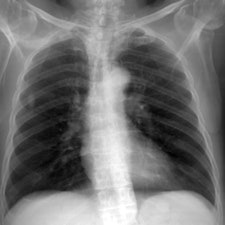

They tested the model in a "virtual clinical trial" in which four experienced image evaluators graded images of average and obese adult patients at different potentials, receptor doses, and scatter rejection techniques on an Agfa HealthCare CR system using MD-4.0 phosphor plates. The quality of the images was evaluated using visually graded analysis. The researchers also assessed the influence of rib contrast.

For average-sized patients, image quality improved when tube potential was reduced compared with the reference (102 kVp) and no scatter rejection was indicated. For obese patients, it has been shown that an antiscatter grid is indicated and should be used in conjunction with as low a tube potential as possible (while allowing exposure times, 20 msec), the researchers wrote. It is also possible to reduce receptor air kerma by 50% without adversely influencing image quality. They also found rib contrast did not interfere at any tube potential.

In 50 average patients who were reconstructed without scatter rejection, readers gave higher marks for images acquired with lower tube potential (kVp) settings, demonstrating that image quality improves with lower kVp, the researchers said. Visual grading analysis system scores ranged from 0.41 for 50 kVp to 0.03 for 109 kVp, but there was very little difference between image quality at tube potentials greater than 102 kVp (0.03 at 109 kVp to 0.07 at 150 kVp), according to the authors.